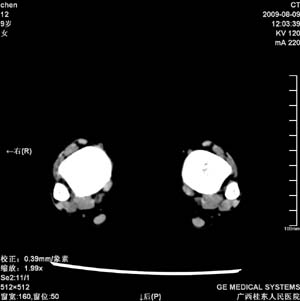

标题: PED2867:右侧内踝肿胀,骨质改变,请各位老师会诊 [打印本页]

标题: PED2867:右侧内踝肿胀,骨质改变,请各位老师会诊

九岁小朋友,近期左侧内踝疼痛,局部肿胀,平时无特殊,近期经常溜干冰

对不起,是右侧内踝肿胀

双踝关节骨质及发育未见异常。

左侧内踝密度增高,请结合临床!